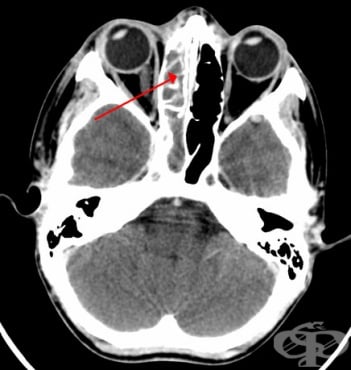

За поставяне на диагнозата остър синузит имат значение симптомите на пациента, лабораторните изследвания на кръвта, рентгенография на околоносните синуси, при необходимост и компютърна томография. При хроничен синузит е добре да се направи и микробиологично изследване. Болният трябва да отиде на л...

Синузит Възпалени синуси Синузит Симптоми при синузит Синузит Синузит Риноскопия Рентгенография максиларен синузит Компютърна томография етмоидакен синузит ЯМР синузит Одонтогенен синузит Лечение на синузит

СинузитВъзпалени синусиСинузитСимптоми при синузитСинузитСинузитРиноскопияРентгенография максиларен синузитКомпютърна томография етмоидакен синузитЯМР синузитОдонтогенен синузитЛечение на синузитЛечение на синузит